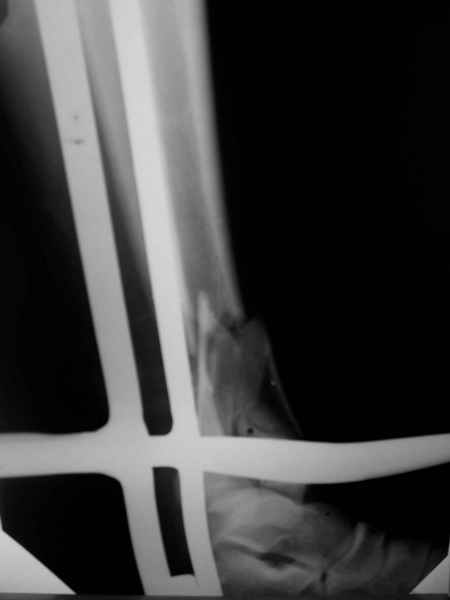

1. Представленные рентгенограммы во-превых плохого качества (ну да ерунда), а во-вторых (самое главное) - в нестандартных проекциях. Невозможно оценить количество и положение фрагментов суставной поврехности. Собственно это делает обсуждение бессмысленным. Мы обсуждаем не конкретный случай, а вообще...

2. Независимо от этого основная проблема - не в фиксации, а в репозиции. Жаль, что не сделали сразу. Видимо, придется открываться.

3. Оптимальным представляется сочетание следующих компонентов:

- внешний остеосинтез

- открытая репозиция

- допольнительная фиксация крупных фрагментов винтами с целью сокращения сроков внешней фиксации.